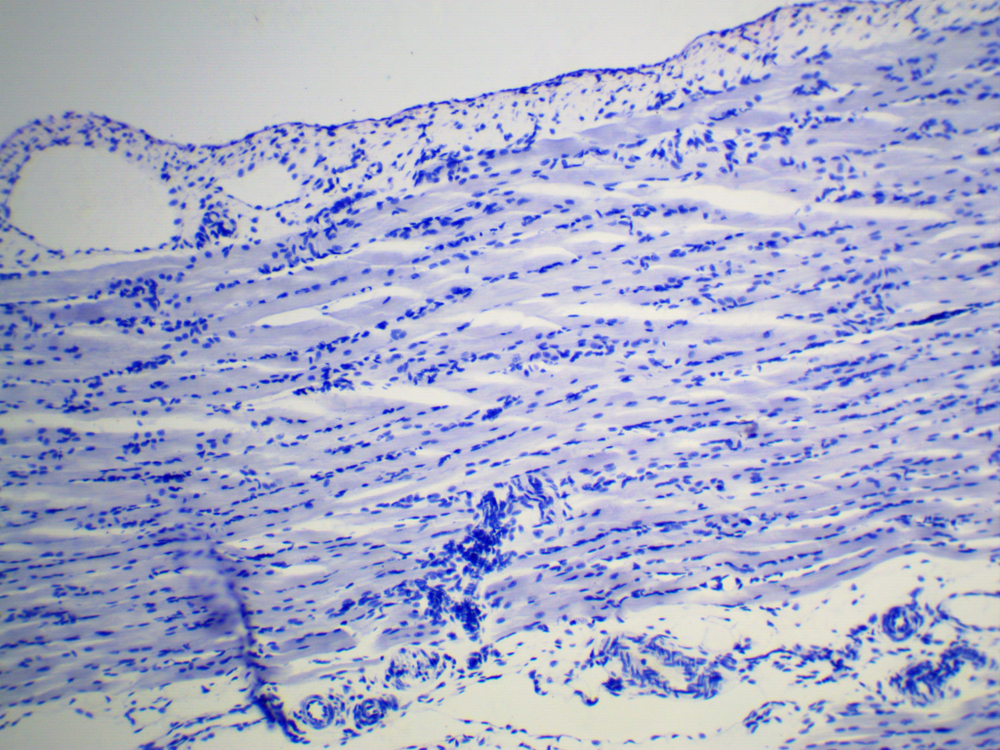

Камера ToupCam UCMOS05100KPA c сенсором Aptina® AR0521 представляет собой сенсор CMOS формата 1/2.5 дюйма, с количеством активных пикселей 2592 по горизонтали и 1944 по вертикали. Камера, благодаря однокристальной структуре, позволяет использовать оконный режим;возможности пропуска колонн и рядов и возможность получения мгновенного снимка предпросмотра (т.н. “snapshot”).

В камере используется технология обработки изображения Ultra-Fine Color Engine которая помимо использования процесса демозаики и настройки баланса белого включает в себя коррекцию “горячих пикселей” , конверсию цветового пространства, кросс-канальную коррекцию, коррекцию цветовых параметров, гамма коррекции и так далее.